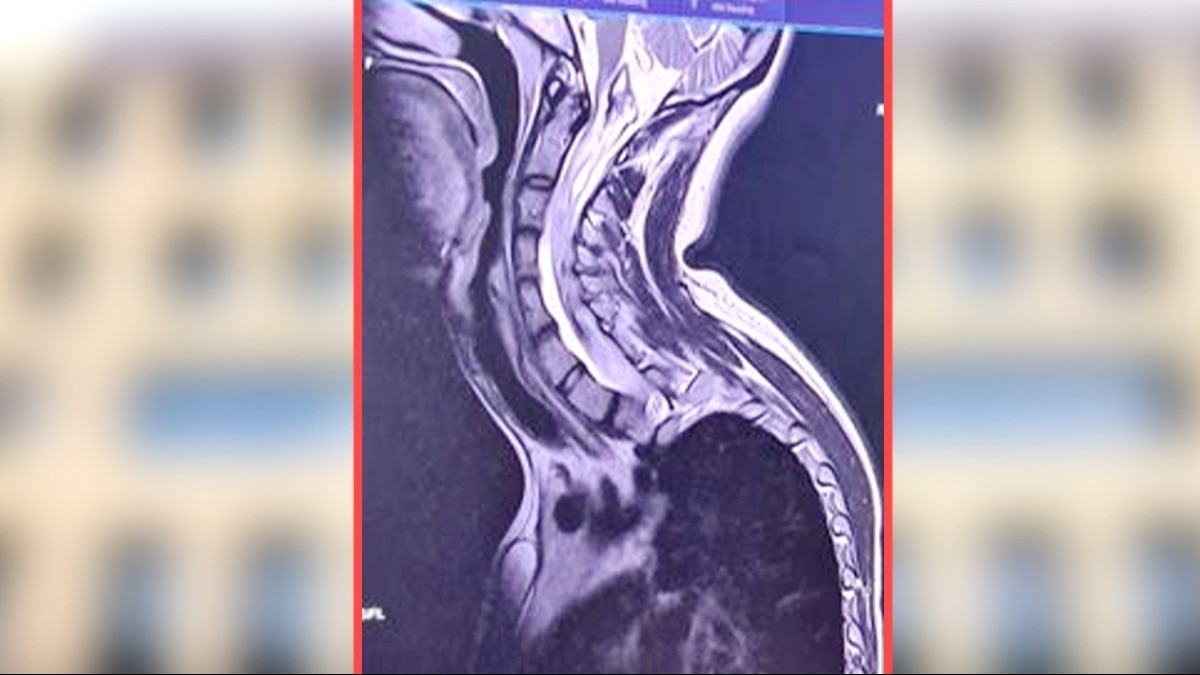

रेडियोलॉजी विभाग में पूरी रीढ़ की हड्डी का एम.आर.आई किया गया. जांच में एक इंट्रामेडुलरी ट्यूमर दिखा जो सर्विकोमेडुलरी जंक्शन से डी11 वर्टिब्रा तक फैला हुआ था. यह अधिक चुनौतीपूर्ण था क्योंकि मरीज को स्कोलियोसिस था.

मरीज की सर्वाइकल से डी12 वर्टिब्रा तक लैमिनोटॉमी की गई. ट्यूमर को पूरी तरह से काट दिया गया और 15 घंटे तक चले ऑपरेशन में मामला ख़त्म हो गया. यह ट्यूमर करीब 40 सेंटीमीटर तक लंबा था. ट्यूमर हटाने के बाद स्पाइन लैमिनोटॉमी को मिनी प्लेट और स्क्रू से ठीक किया गया.